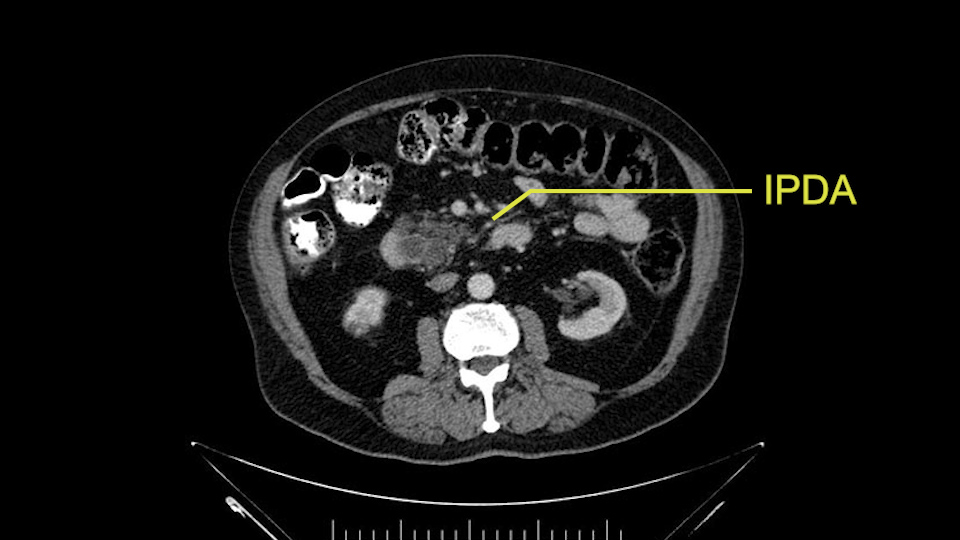

Then look at the first jejunal branch - which is this thing here - this little branch which goes under the SMA. It’s something that we’ve just started appreciating over the past few years and the reason for that is: there’s two or three small branches that come out of the uncinate into the the first jejunal and it’s a fairly inevitable part of the operation where there’s some bleeding. As long as you’re cognizant of what’s happening, it’s no reason to panic and that kind of bleeding will eventually stop or can be stopped but it’s not easy because these little vessels are fragile from the uncinate to the first jejunal. So I do focus on that and it’s pretty consistent I’d say 9 times out of 10, people have that first jejunal.

Other important points are: the dissection of the uncinate process which must be done very carefully, the ligation of the venous branches there, and looking for the inferior pancreaticoduodenal arteries coming from the superior mesenteric artery during the dissection of the uncinate process.

Uncinate margin, IPDA

Once the pancreatic neck is divided, you sort of roll or flip the neck of the gland over, exposing the anterior surface and the right lateral surface of the portal vein-SMV complex. Continue that dissection down. Oftentimes you can really continue your dissection right along the uncinate on the SMA. Again a little advantage of this patient having an ampullary lesion, there's likely to be no evidence of extension into the uncinate so you don't have to worry quite as much about the margin at the uncinate as you would with a pancreatic head cancer. Keeping in mind that you will have an inferior pancreatic duodenal artery in there that you want to try to identify and ligate individually. At some point along that time I go to the ligament of Treitz. Clean an area of the ligament of Treitz of its mesentery, divide it there with a linear stapler. I use the Harmonic scalpel to mobilize the proximal 10-inches or so of small intestine down to the ligament of Treitz completely mobilize the ligament of Treitz past the jejunal limb underneath the root of the mesentery and then carefully dissect the third and fourth portion of the duodenum’s mesentery as well as the remaining uncinate to complete my resection. I will have marked and sent frozen section from the pancreatic neck at the time that I do the resection of that part of the gland so that I have that information back by now. I would also probably get a margin on the uncinate and a margin on the bile duct just for completeness, although for an ampullary carcinoma that would be unlikely to have a positive extension.